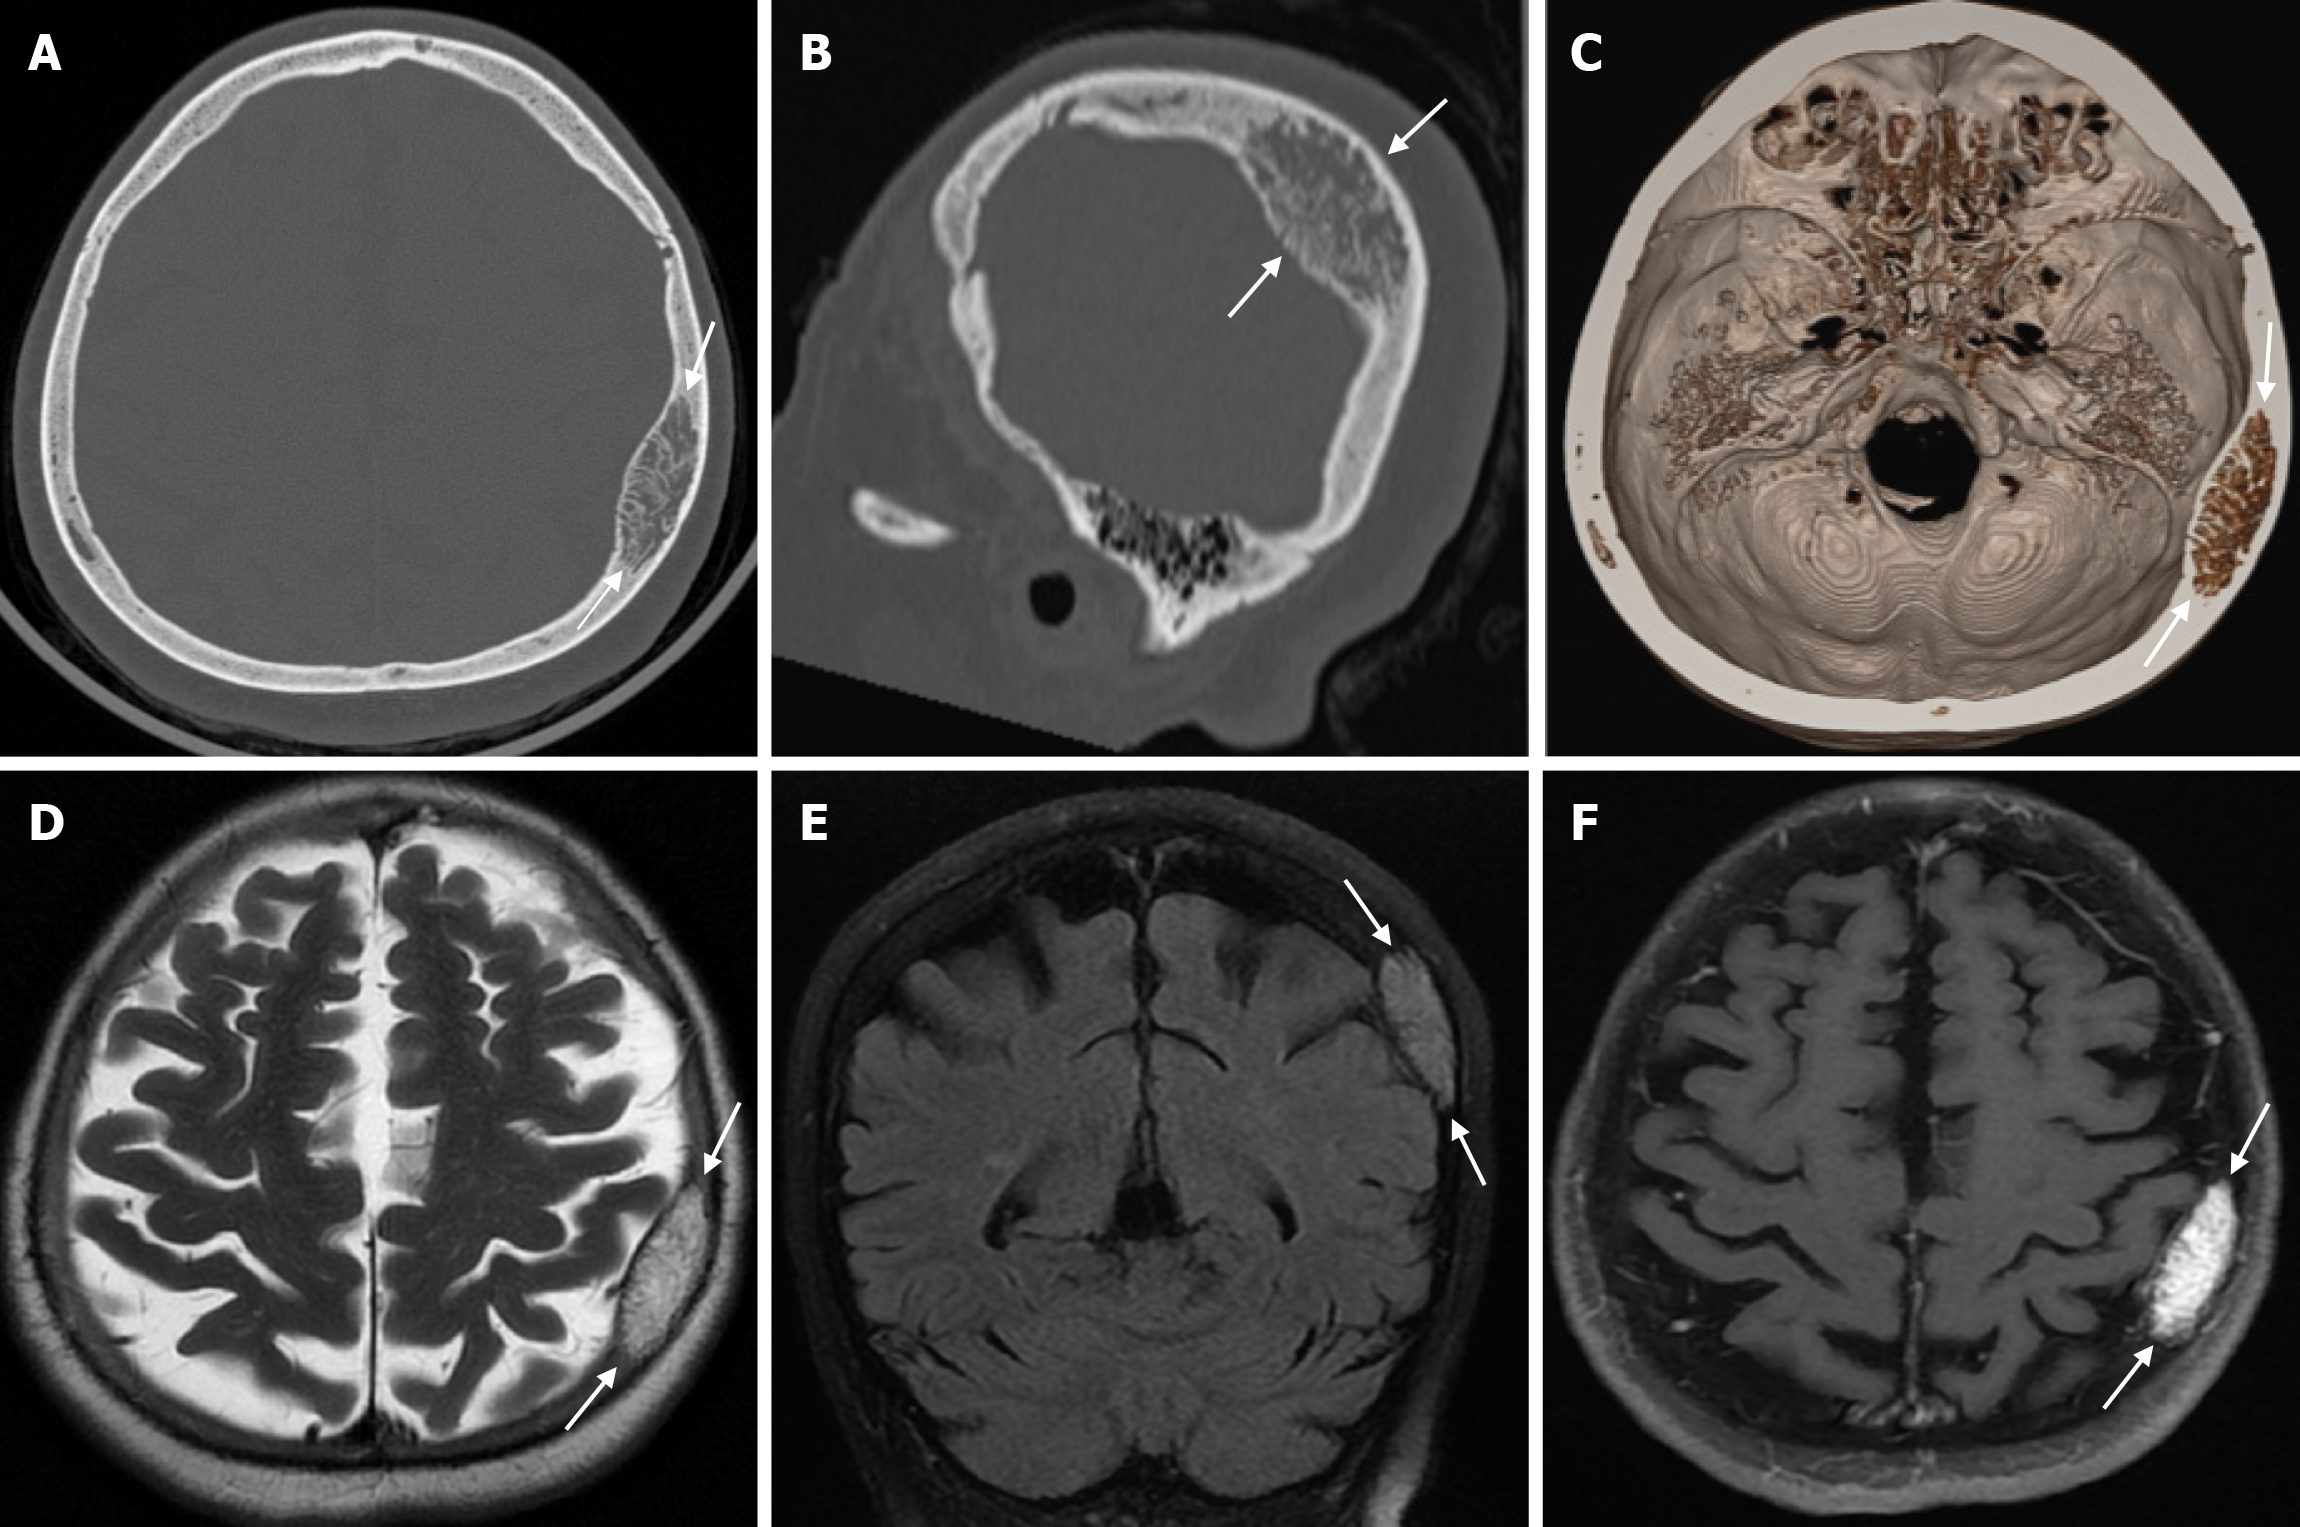

Sinus pericranii is a rare vascular anomaly with transosseous venous channels connecting the intracranial venous system to the extracranial veins[26]. It is usually congenital, but trauma is thought to be a predisposing factor. The congenital lesion has an endothelial lining, while the acquired lesion has a connective tissue lining. The male to female ratio is 2/1 and the condition can be seen in all age groups, but is usually diagnosed before the age of 30. Sinus pericranii is most commonly located near the midline. The frontal region is most commonly involved, followed by the parietal and occipital regions, while lateral localization is rare[27]. Sinus pericranii is often associated with other intracranial venous anomalies, such as developmental venous anomalies or venous vascular malformations. Affected patients typically present with a soft cutaneous mass that expands in the supine position or during the Valsalva manoeuvre and contracts on standing. Patients are usually asymptomatic, but headache, dizziness or nausea may occasionally occur. Sinus pericranii is classified as dominant (the majority of venous flow communicates with the sinus pericranii) or accessory (only a portion of intracranial venous flow communicates with the sinus pericranii). CT venography shows a calvarial defect and anomalous communication between the dural venous sinus and the extracranial veins (Figure 7). Thrombosis of the dominant sinus pericranii, where most intracranial venous drainage occurs, is associated with life-threatening complications such as venous congestion and/or infarction. Treatment is contraindicated in the dominant type. For accessory sinus pericranii, interventional (i.e. surgical or endovascular) treatment may be indicated to improve symptoms, prevent future traumatic haemorrhage and air embolism, and for cosmetic reasons[26]. Sinus pericranii should be suspected when a soft, fluctuant mass is detected near the intracranial sinus and can vary in size. MRI shows the relationship of the lesion to the underlying sinus, while direct injection of contrast medium through the wall of the mass shows rapid passage of contrast into the sinus[27]. Also, MRI shows variable signal intensity due to flow artefacts[26].

Leptomeningeal cysts can develop as a rare complication of linear skull fractures in children. The incidence is reported in the literature to be between 0.05% and 0.1%. They are usually seen in children under the age of 3. These cysts most commonly occur in the cranial convexity but can also be seen in the posterior fossa and orbital roof. This complication develops as a result of dural tear associated with skull fracture. Laceration of the dura mater leads to herniation of the leptomeninges and filling with CSF. The continuous pulsatile pressure of the CSF and the expansion of the cyst cause resorption of the adjacent bone, erosion of the bone edges and expansion of the skull fracture. The fracture site, together with the thickness of the soft tissues, can be seen on plain radiography. While bone fractures can be better demonstrated with CT imaging, MRI is more useful in distinguishing leptomeningeal cysts from other pathologies. Leptomeningeal cysts are isointense with cerebrospinal fluid on both T1-weighted and T2-weighted images (Figure 10). Associated pathologies such as subdural fluid collections, hematomas, encephalomalacia, and ventricular dilatation may also be seen on CT imaging and MRI. Early diagnosis is important because of the risk of neurological deterioration and seizures, and treatment includes dural repair and cranioplasty[35].